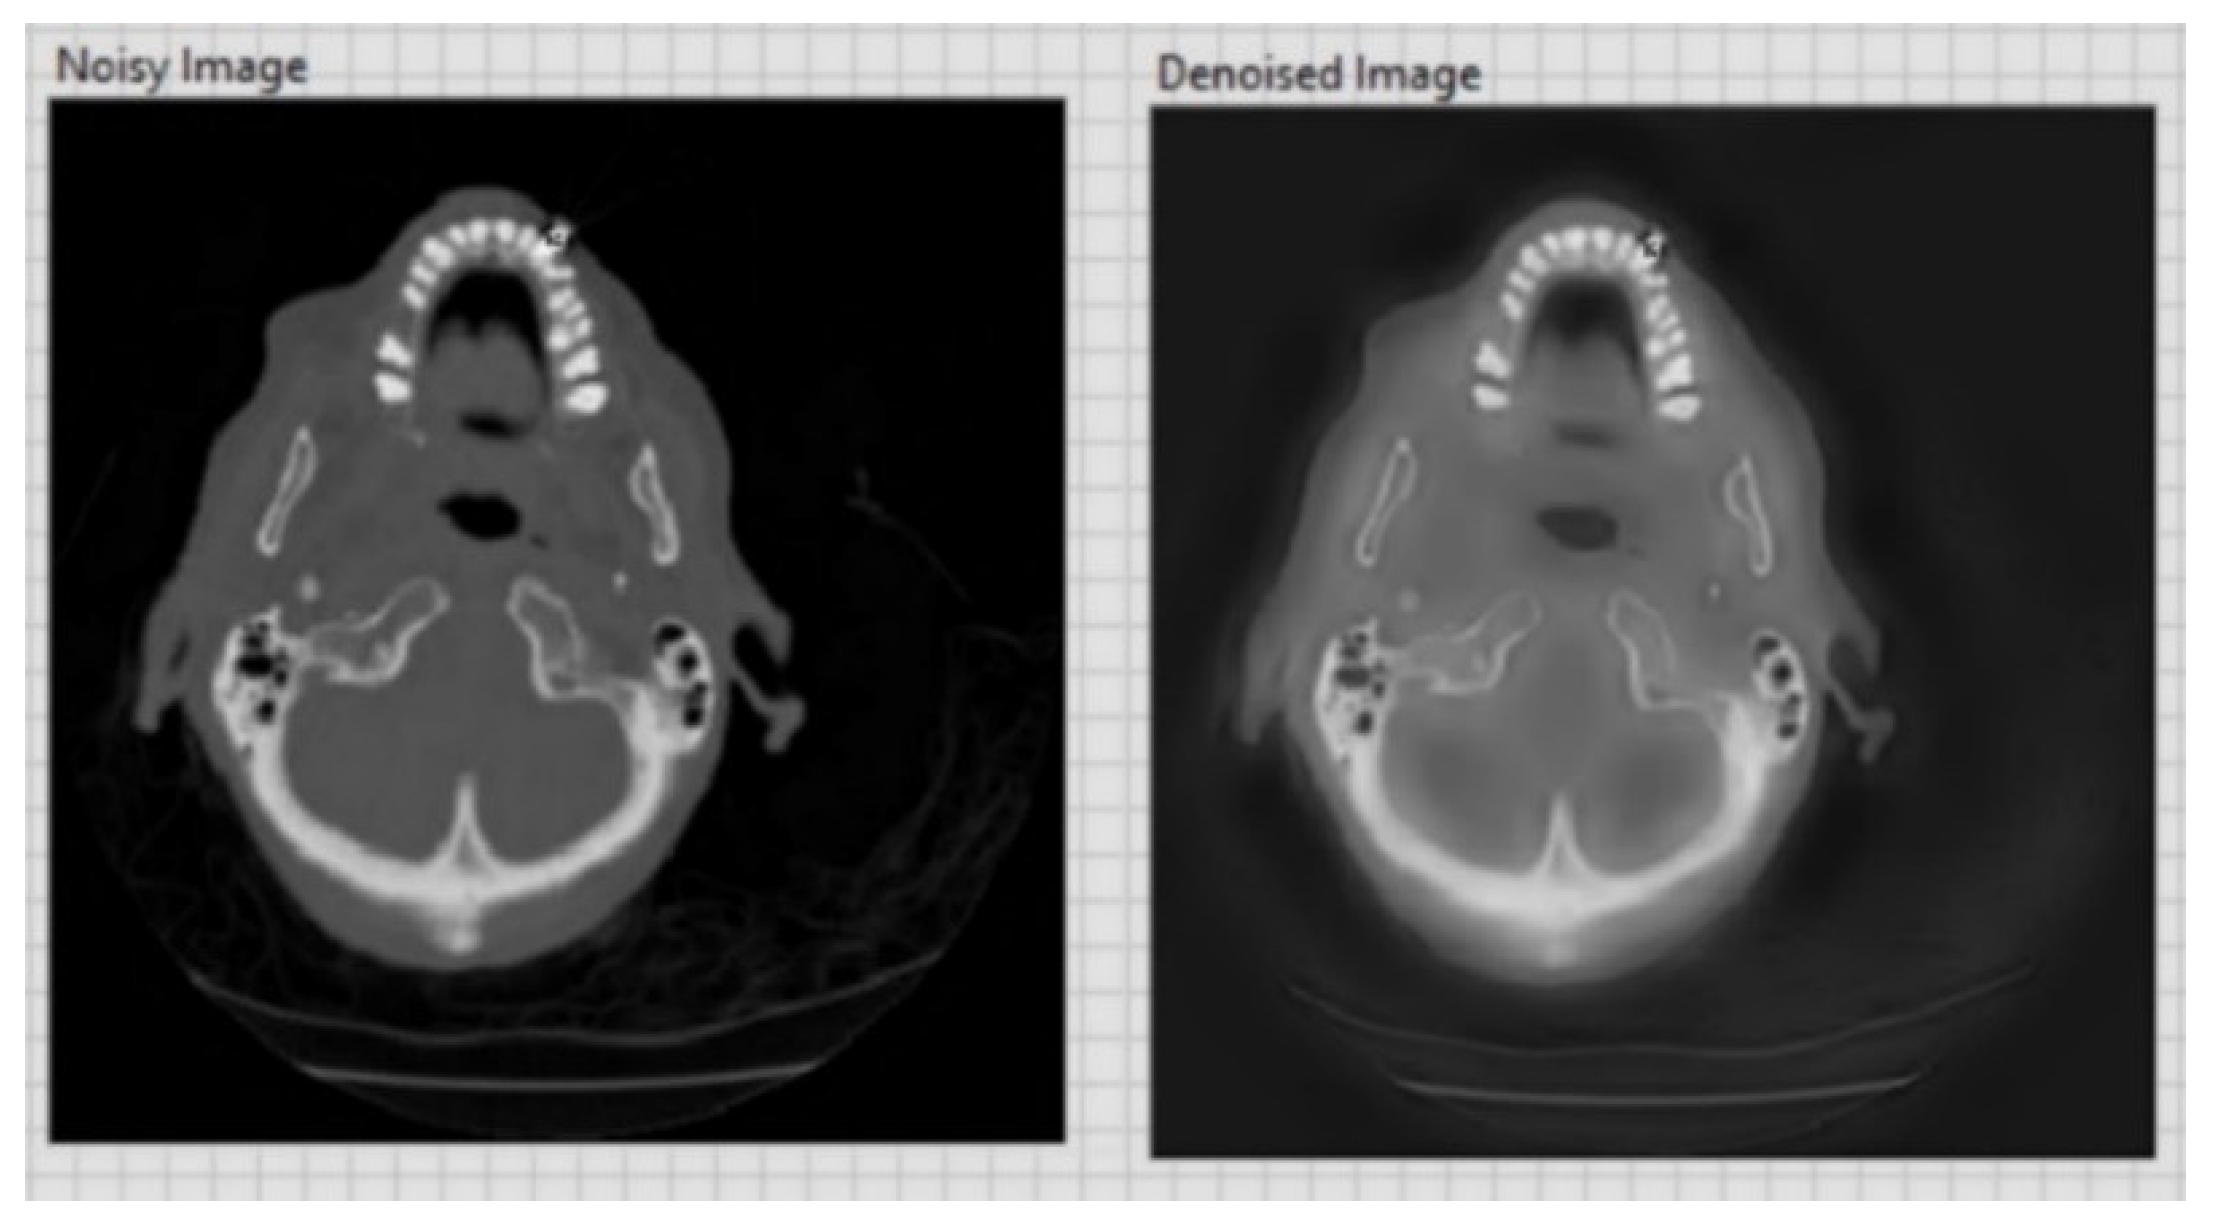

| CT image (Figure 8) 256 × 256 | 20.13 | 0.1 |

| CT image (Figure 9) 256 × 256 | 26.09 | 0.05 |